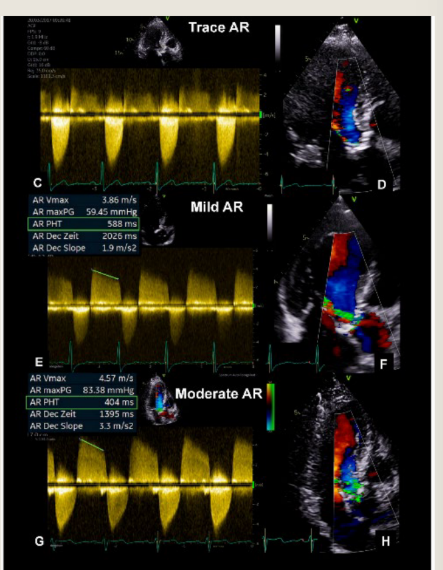

Assessment begins in what view

Color doppler shows the presence of what

measure what

Assessment begins in PLAX

Color Doppler shows the presence of

aortic regurgitation

Measure the LVEDD for LV dilatation

Aorta measurements including Sinus of

Valsalva, ST junction, and proximal aorta

Valve etiology

CW Doppler

Density proportional to what

Density of signal increase as what increase

how does Mild regurgitation show up

how does Severe Regurgitation show up

Sensity proportional to RBCās

Density of signal increase as RV increase

Mild R

Faint Doppler signal

Difficult to obtain

Severe R

Dense Doppler signal

Shape of CW Doppler reflects?

Severe AR may become asymmetrical

reflecting

Shape of CW Doppler reflects pressure

changes

reflecting rapid equalization of pressure